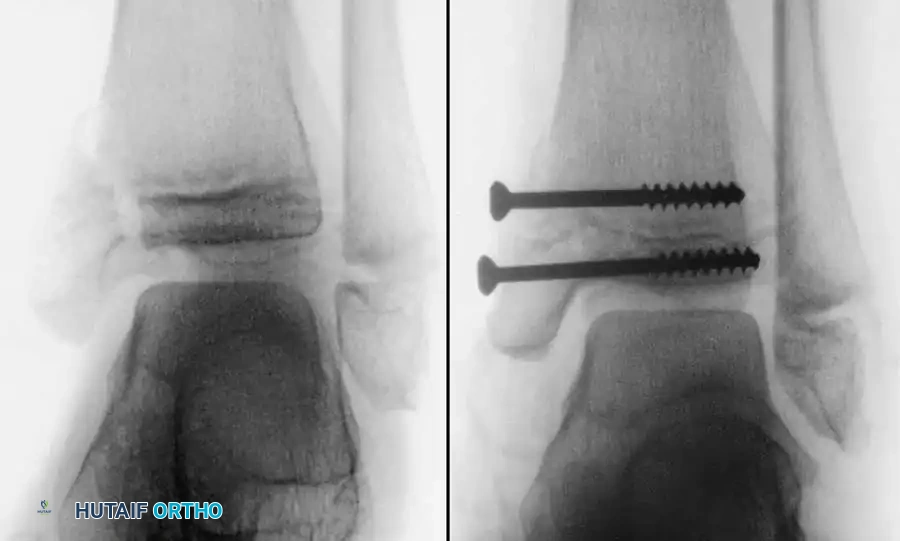

Fig. 33-175: Fixation of a tongue-type Salter-Harris III fracture utilizing cancellous screws.

5. Fixation:

* For vertical fracture components, insert transverse guide pins.

* In older children and adolescents nearing skeletal maturity, utilize 4.0mm or 4.5mm partially threaded cancellous bone screws to achieve interfragmentary compression.

* In younger children with significant remaining growth potential, utilize smooth Kirschner wires (K-wires) placed transversely or horizontally to minimize the risk of physeal arrest.

Placement of transverse fixation pins.

Final construct utilizing cancellous screws for rigid fixation.